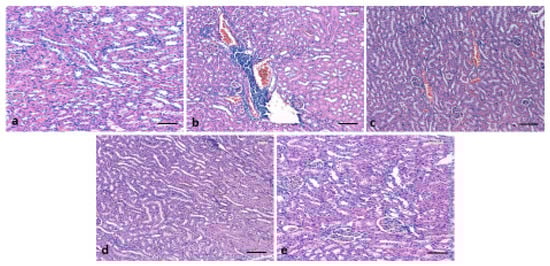

3.6. Effect of 6-Gingerol on Kidney Architecture

3.7. Effects of 6-Gingerol on TNF-α Expression